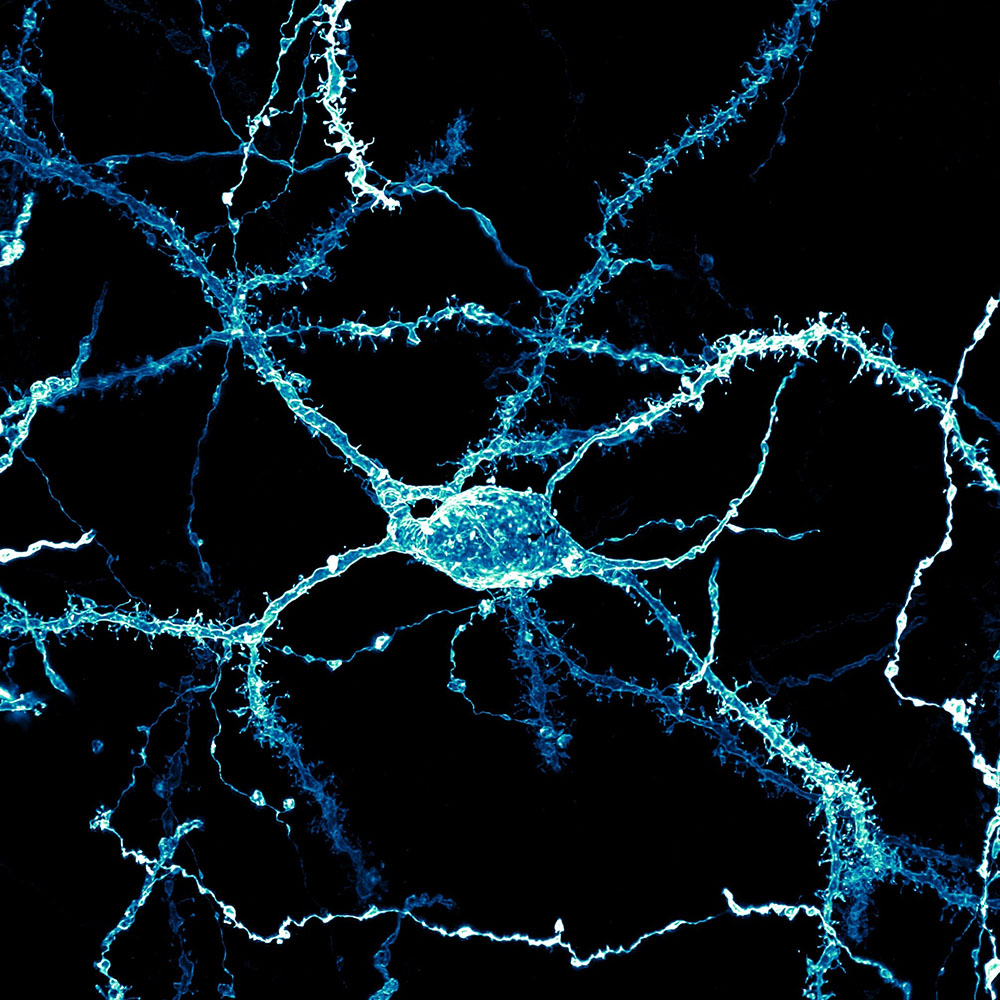

Δείτε και ορισμένες ακόμη που φτάσανε στο τοπ 10 των καλύτερων εικόνων από τον 50ό διαγωνισμό Nikon Small World Photomicrography (κατά σειρά, από την τέταρτη μέχρι τη δέκατη θέση)